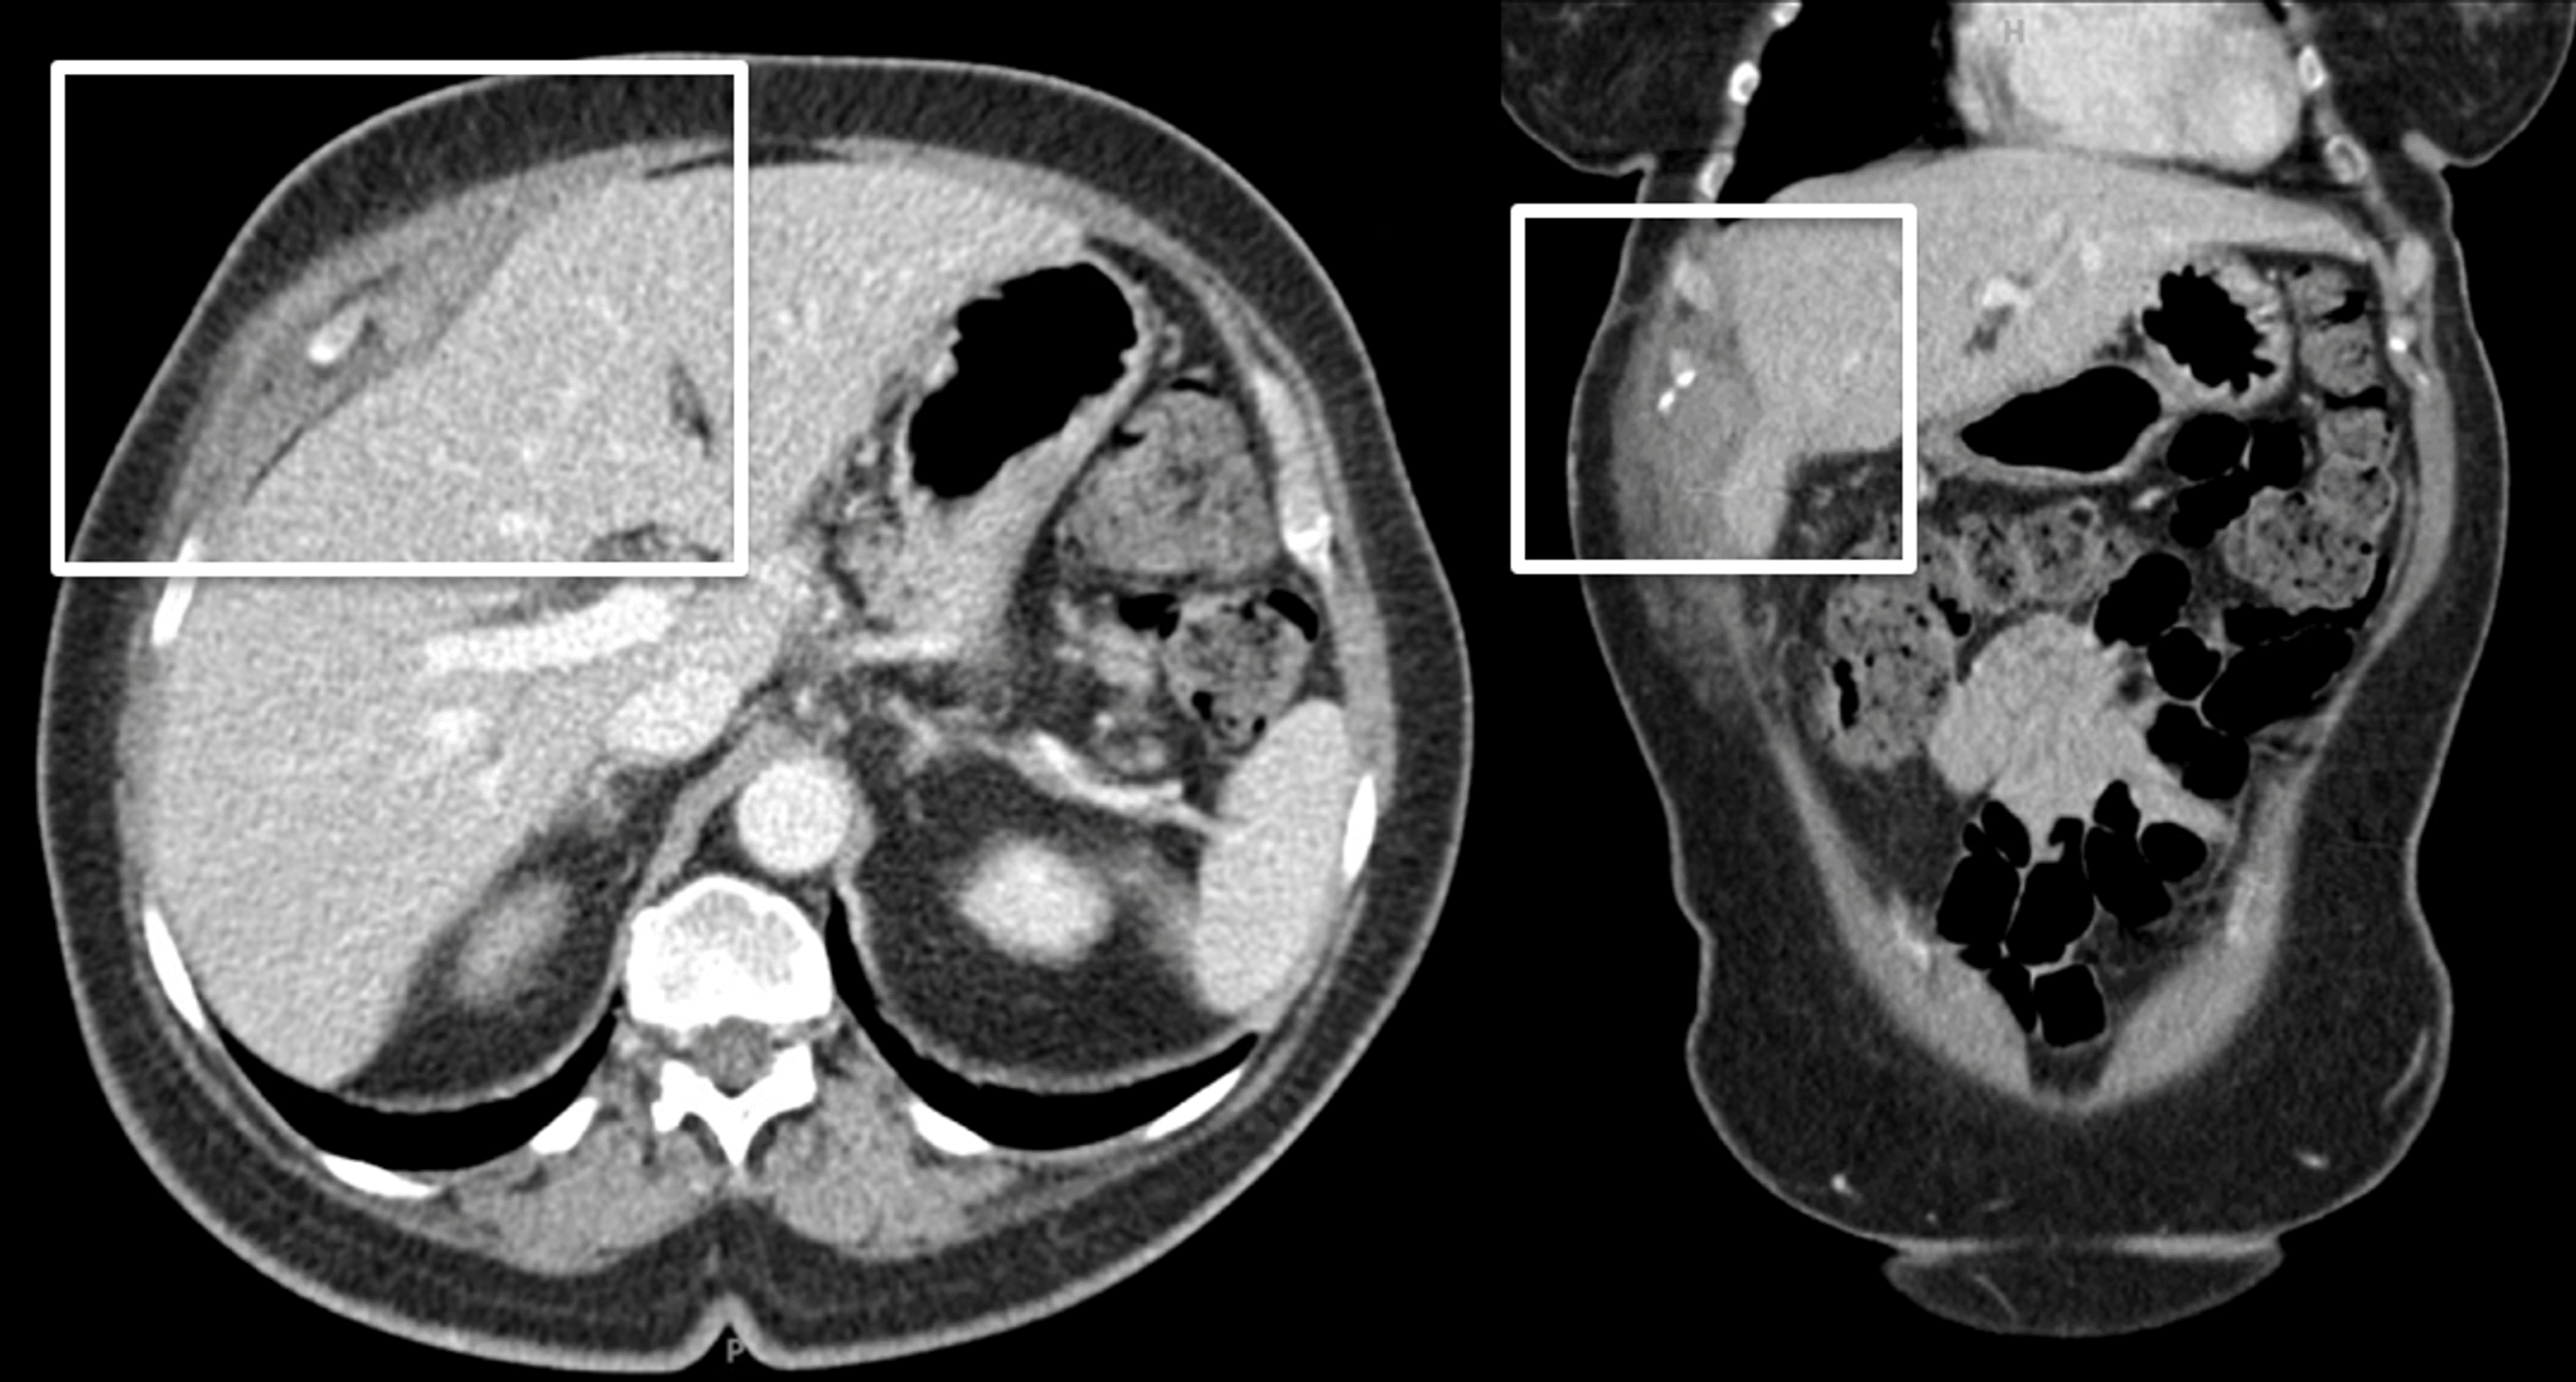

Subcapsular Fluid Collection in the Liver Liver Case Studies CTisus Fluid Collection Post Cholecystectomy The safety of this surgery notwithstanding, the sheer volume of operations results in a notable incidence. The collection of as much as 60 ml of fluid in the gallbladder fossa soon after laparoscopic cholecystectomy. Imaging studies may be required to look for evidence of biloma, abscess collections, or hematomas. Bile collections are usually close to the site of the leak,. Fluid Collection Post Cholecystectomy.

Abdomen CT scan showed complicated fluid collection in gallbladder bed Fluid Collection Post Cholecystectomy These fluid collections have a high risk of infection after cholecystectomy for acute cholecystitis. If a fluid collection is identified on. The collection of as much as 60 ml of fluid in the gallbladder fossa soon after laparoscopic cholecystectomy. The safety of this surgery notwithstanding, the sheer volume of operations results in a notable incidence. Imaging studies may be required. Fluid Collection Post Cholecystectomy.

Computed tomography after laparoscopic cholecystectomy demonstrating an Fluid Collection Post Cholecystectomy Imaging studies may be required to look for evidence of biloma, abscess collections, or hematomas. Ct and us of a bile leak often show a small to moderate amount of. If a fluid collection is identified on. Bile collections are usually close to the site of the leak, but occasionally they may be remote or may even be intrahepatic. The. Fluid Collection Post Cholecystectomy.